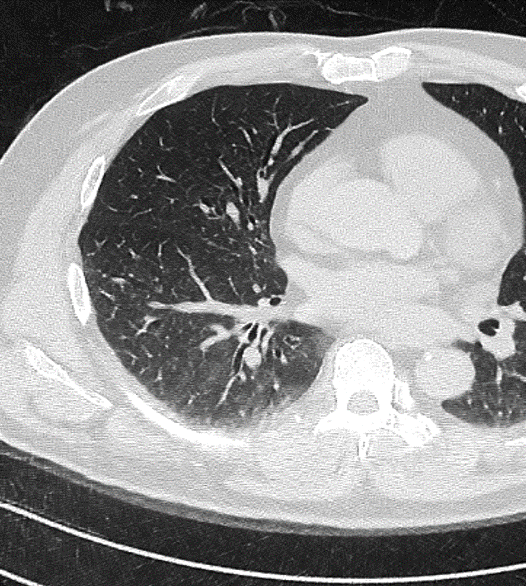

클라리파이 AI 솔루션

- ClariCT.AI

CT 영상 잡음저감 및 화질 향상

ULD Chest CT image (10% of normal dose, 0.2 mSv, FBP) -

Predicted Noise w| ClariCT.AI -

Noise subtracted image